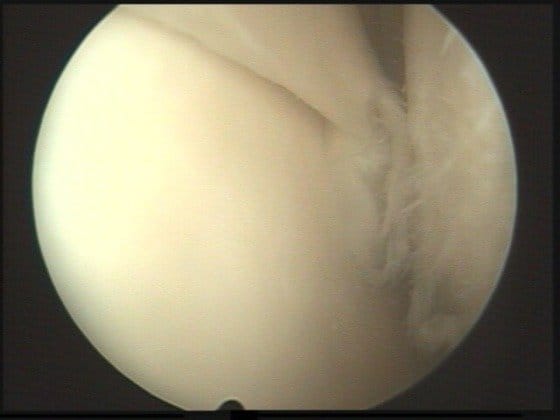

artroskopia05b